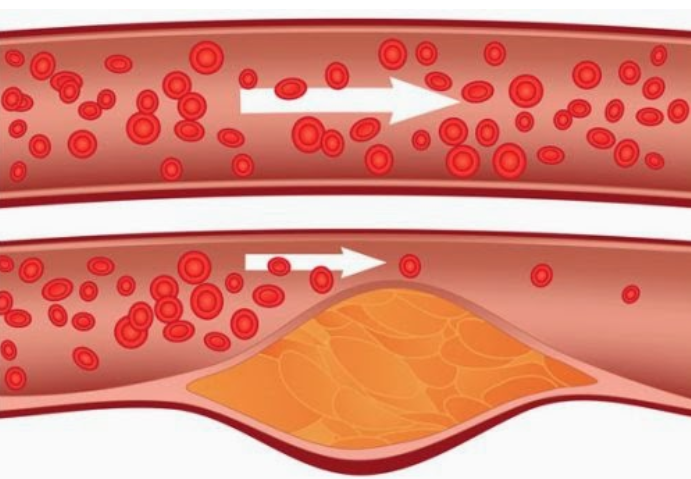

6. High blood cholesterol is a major cause of heart disease and strokes. The saturated fat that is primarily found in meat increases our cholesterol levels.

So, when you stop eating meat, your cholesterol level remains within normal limits. According to Forks Over Knives, when people eat a plant-based diet, their blood cholesterol levels drop by up to 35%.